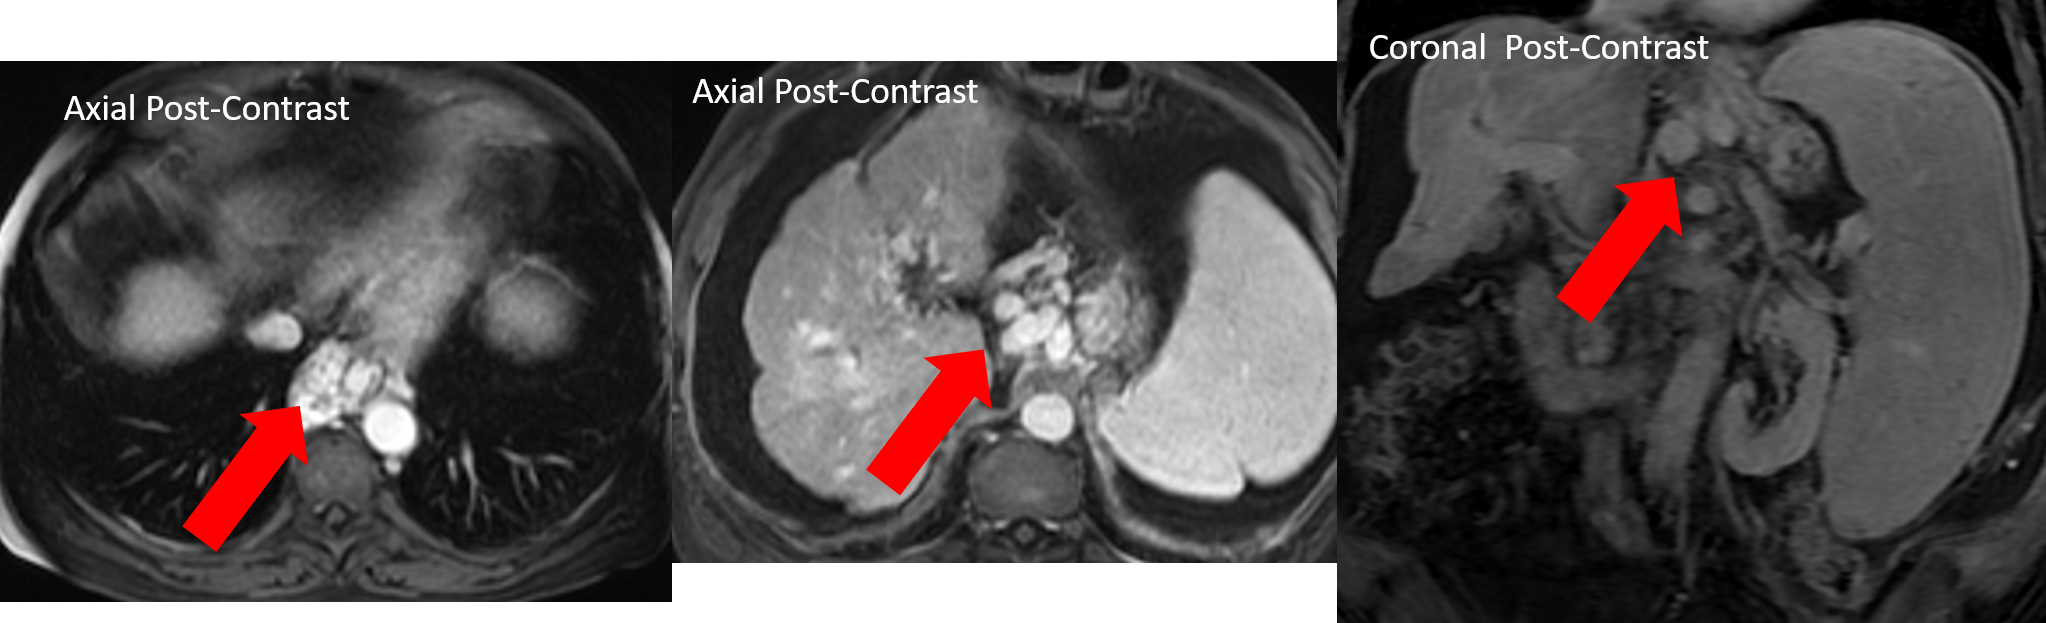

Web scaling ai applications for radiology. Web radiology publishes cutting edge and impactful imaging research articles in radiology and medical imaging in order to help improve human health. Computed tomography magnetic resonance imaging.